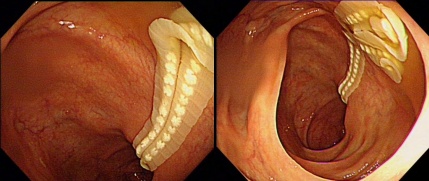

光滑的结肠出现一截白色“布条”状物,紧紧扒在粉红色肠壁上,一动不动,是那么突兀。随着镜头继续推进,根本看不见尽头。

5分钟后,“布条”蠕动了一下。啊!所有人都吓一跳:

它是活的。

大家面面相觑——这是一条活的寄生虫。

章医生尽量抓取寄生虫,太长了,真是太长了,最终取出60cm。